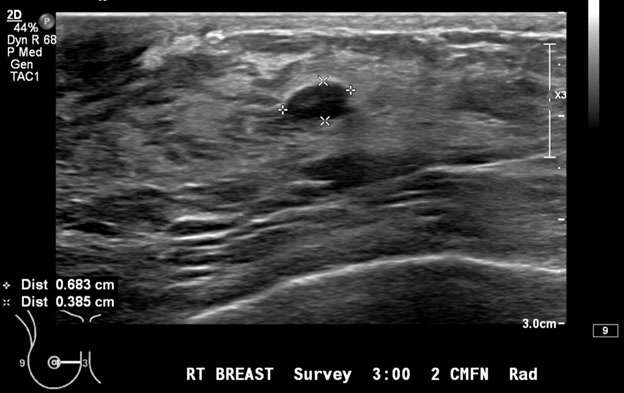

1. Oval: an oval mass (Figure 1) is elliptical or egg-shaped (may include two or three undulations).

Mammography: Masses Figure 1

Figure 1: Targeted ultrasound examination of the right breast demonstrated an oval mass with circumscribed margins measuring 7 x 4 x 7 mm seen at 3 o'clock located 2 centimeters from the nipple. Oval mass is probably benign, sonographic follow-up in 6 months is recommended. BI-RADS Category 3: Probably Benign Finding.